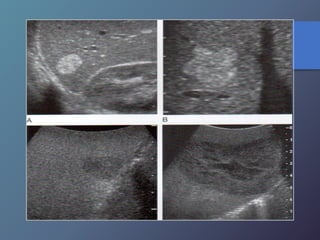

Metástasis

• Su incidencia depende del tipo de tumor.

• Localizaciones mas frecuentes del TU primario:

vesícula biliar, colon, estomago, páncreas, mama y

pulmón.

• Pueden presentar una sola lesión hepática, aunque

suelen tener múltiples masas focales.

Mt Hiperecoicas

• Ecográficamente se presentan las lesiones

de tamaño variable con presencia de un

halo hipoecoico.

• Diferenciar lesiones malignas de benignas

por presencia de halo hipoecoico.

• Se describen como lesiones ecógenas,

hipoecoicas, en diana, calcificadas,

quísticas y difusas.

Clasificación de las Metástasis

Metástasis • Su incidenciadepende del tipo de tumor. • Localizaciones mas frecuentes del TU primario: vesícula biliar, colon, estomago, páncreas, mama y pulmón. • Pueden presentar una sola lesión hepática, aunque suelen tener múltiples masas focales. Mt Hiperecoicas

• 71.

• Ecográficamente sepresentan las lesiones de tamaño variable con presencia de un halo hipoecoico. • Diferenciar lesiones malignas de benignas por presencia de halo hipoecoico. • Se describen como lesiones ecógenas, hipoecoicas, en diana, calcificadas, quísticas y difusas.